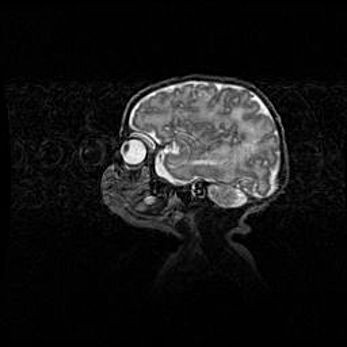

Церебральная ишемия II.

Возраст: 5 дней

Вес: 3400 г

Пол: женский

Окружность головы: 35 см

Срок гестации: 39 недель

Церебральная ишемия – это заболевание, характеризующееся недостаточностью (гипоксией) либо полным прекращением (аноксией) снабжения мозга кислородом по причине закупорки одного или нескольких сосудов. Это приводит к  что метаболическим расстройствам различной степени тяжести в тканях головного мозга, развитию коагуляционных некрозов и гибели нейронов.